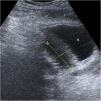

Classification of acute diverticulitis in the left colon with ultrasonography and computed tomography: Value of current severity classification schemes

The current management of acute diverticulitis of the left colon (ADLC) requires tests with high prognostic value. This paper analyzes the usefulness of ultrasonography (US) in the initial diagnosis of ADLC and the validity of current classifications schemes for ADLC.

This retrospective observational study included patients with ADLC scheduled to undergo US or computed tomography (CT) following a clinical algorithm. According to the imaging findings, ADLC was classified as mild, locally complicated, or complicated. We analyzed the efficacy of US in the initial diagnosis and the reasons why CT was used as the first-line technique. We compared the findings with published classifications schemes for ADLC.

A total of 311 patients were diagnosed with acute diverticulitis; 183 had ADLC, classified at imaging as mild in 104, locally complicated in 60, and complicated in 19. The diagnosis was reached by US alone in 98 patients, by CT alone in 77, and by combined US and CT in 8. The main reasons for using CT as the first-line technique were the radiologist’s lack of experience in abdominal US and the unavailability of a radiologists on call. Six patients diagnosed by US were reexamined by CT, but the classification changed in only three. None of the published classification schemes included all the imaging findings.

US should be the first-line imaging technique in patients with suspected ADLC. Various laboratory and imaging findings are useful in establishing the prognosis of ADLC. New schemes to classify the severity of ADLC are necessary to ensure optimal clinical decision making.